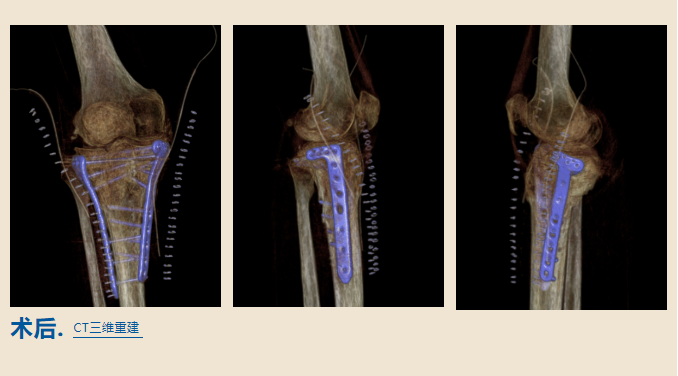

1月10日

桐柏路院区接受了手术

由查晔军院长

和成人ai

创伤骨科主任刘国会联合手术

手术进行了整整两个小时

专家们非常仔细地操作着每一个步骤

当手术结束后

医生告诉王大姐

非常成功

她的腿将会逐渐恢复到正常状态